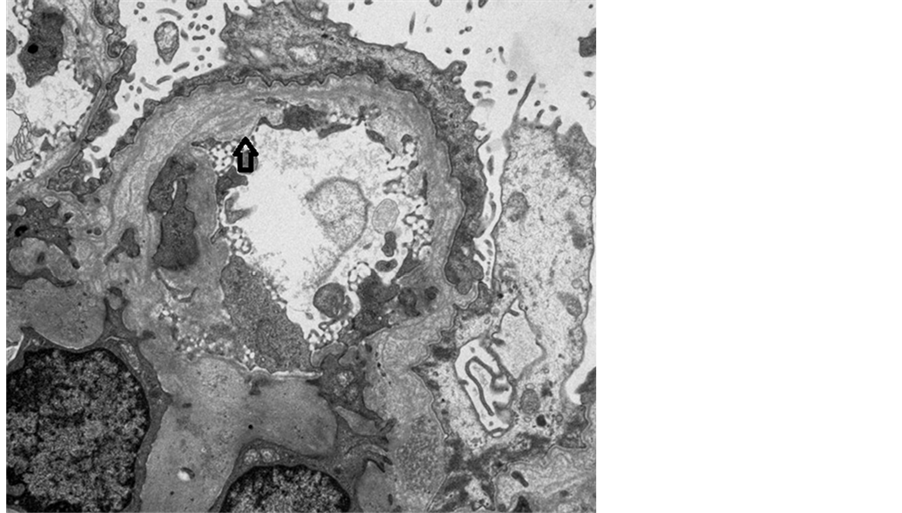

A 12-year-old girl presented with puffy face, bilateral lower-leg edema and frothy urine in recent two months. Biochemical studies showed nephrotic range proteinuria, hematuria > 30 erythrocytes per high-power field, lipiduria, serum cholesterol 10.1 mmol/l, albumin 16 g/l, and creatinine 30.5 mmol/l. Her blood pressure was 108/70 mmHg, and renin-angiotensin system blockers were not used. A kidney biopsy was performed for her nephrotic-nephritic syndrome with unclear etiology. Light microscopic examination with hematoxylin and eosin stain revealed rigidity and moderate thickening of the glomerular basement membrane (GBM), and segmental glomerular sclerosis. Accumulating an excessive amount of neutral fats in renal tubular cells led to extremely foamy appearance and luminal obliteration (Figure 1). Such fatty change is followed by necrosis of injured cells and detachement from the basement membranes compounding luminal obliteration. Electron microscopy depicted irregular distribution of GBM with basket-weave appearance (thinning, thickening, splitting and lamination of lamina densa) and diffuse effacement of podocyte foot processes (Figure 2). Myriad intracellular lipid droplets were noted within tubulointerstitial lipid-laden foamy macrophages (Figure 3).

Figure 2. Electron microscopy demonstrated irregular distribution of glomerular basement membrane with basket-weave appearance (thinning, thickening, splitting and lamination of lamina densa; arrow), and effacement of podocyte foot processes.